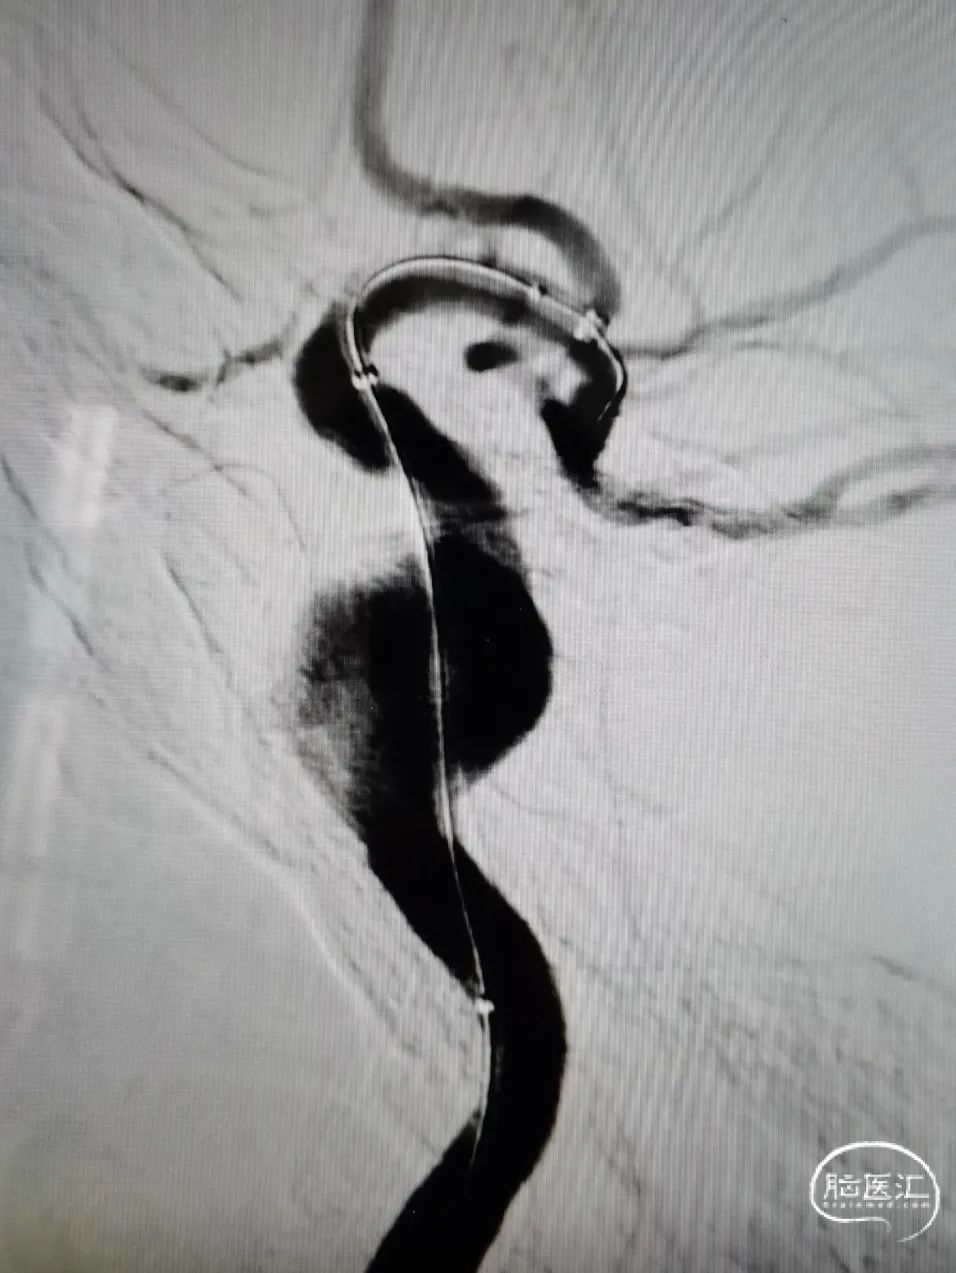

术后造影

术后对比瘤内喷射征明显减少,造影剂滞留明显。行CT重建提示支架贴壁良好,术后顺利复苏,4天后顺利出院。

图6